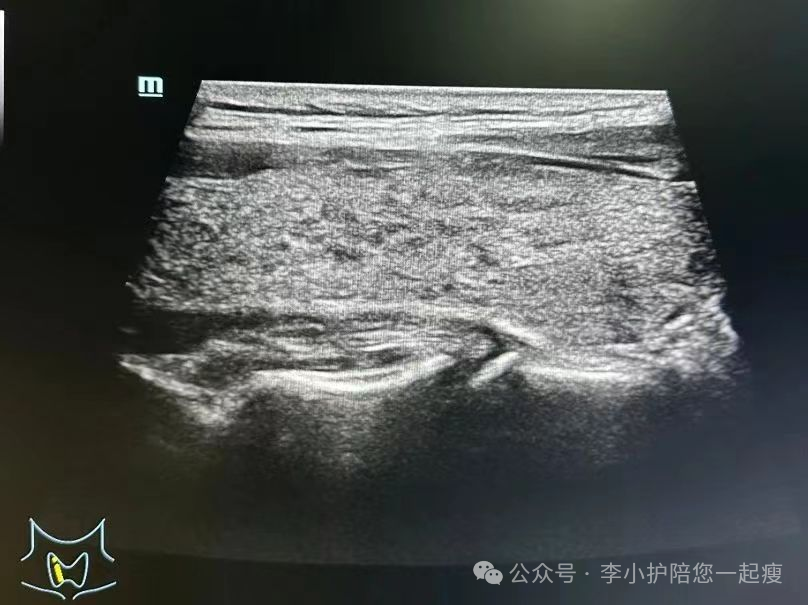

B甲状腺彩超

提示腺体内回声减弱,欠均匀,呈弥漫性改变,可伴多发性低回声区域或者甲状腺结节。